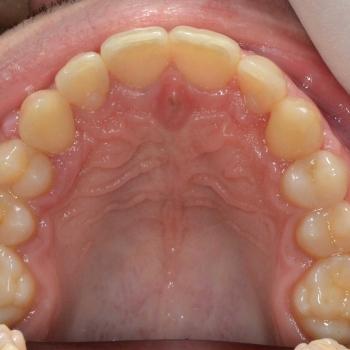

Ádám kitartásának köszönhetően a kezelés végére minden maradó fog a helyére került és egy esztétikailag és funkcionálisan is tökéletes harapást kaptunk.

A kezelés teljes időtartama: 3 év